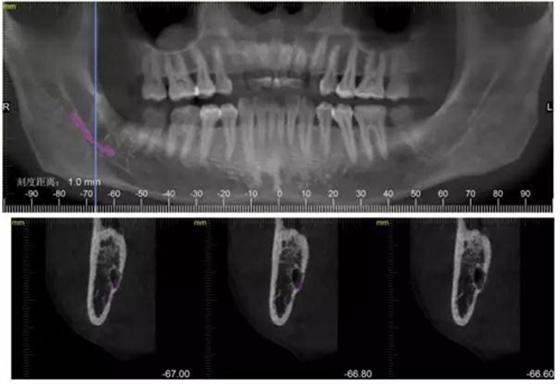

檢查:48號(hào)牙稍偏近中生長(zhǎng),周?chē)例l稍白,遠(yuǎn)中齦袋中有少許滲出物,探診;未出血,叩(--),冷熱(--)。47遠(yuǎn) 中未見(jiàn)齲壞,47冷熱(--)叩(--)。舌側(cè)少許齦上結(jié)石。X線檢查,48遠(yuǎn)中有陰影約2mm,根尖在神經(jīng)管內(nèi)約2--3mm。根尖未見(jiàn)陰影。

下面CBCT,可以看到兩個(gè)牙根的根尖三分之一在神經(jīng)管里面。

CBCT神經(jīng)管標(biāo)線,可以看到標(biāo)線不能連續(xù),中間被阻斷。